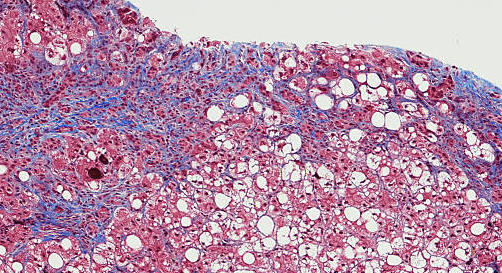

Dans le monde, environ 58 millions de personnes seraient porteuses chroniques du virus de l’hépatite C (VHC). Le nombre de décès annuels avoisine les 290 000, principalement des suites d’une cirrhose ou d’un carcinome hépatocellulaire. En France, l’Assurance maladie estime à 133 000 le nombre de personnes atteintes d’une hépatite C chronique. Une sur trois ignore qu’elle est infectée. « Ces chiffres ont été publiés en 2019 et se réfèrent à une enquête de 2016 », précise Frédéric Chaffraix, responsable du service expert de lutte contre les hépatites virales d’Alsace (Selhva), aux hôpitaux universitaires de Strasbourg (Bas-Rhin). Depuis ? « La crise sanitaire liée au Covid-19 est passée par là », met en garde l’expert, également président de l’association SOS hépatite Alsace-Lorraine. La prévalence de la maladie, en baisse depuis plusieurs années, pourrait ainsi avoir connu un rebond. Les objectifs les plus ambitieux d’éradication de la maladie, évoqués pour l’horizon 2025 en France, s’en trouvent légèrement repoussés.

« La situation a considérablement changé en quelques années seulement », conclut l’experte de l’Afef, qui se veut confiante quant à l’élimination proche de l’hépatite C. Les antiviraux d’action directe, bien que critiqués car coûteux, ont déjà contribué à ce que le virus ne constitue plus la première cause de transplantation hépatique en France. L’amélioration du dépistage précoce irait aussi dans ce sens, en limitant les risques de cirrhose et les accompagnements thérapeutiques lourds.